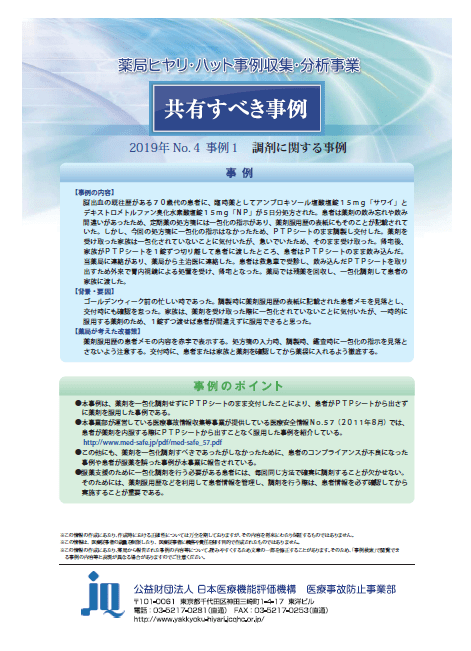

Https Www Nichiyaku Or Jp Assets Uploads Pharmacy Info Ptp Pdf

Https Www Nichiyaku Or Jp Assets Uploads Pharmacy Info Ptp Pdf

Https Www Kuhp Kyoto U Ac Jp Wwwrisk News Jyohou107 Pdf

ptp包装シートの誤飲 平成23年4月 日本薬剤師会 Ppt Download

ptp包装シートの誤飲 平成23年4月 日本薬剤師会 Ppt Download

Https Www Nichiyaku Or Jp Assets Uploads Pharmacy Info Ptp Pdf

Http Www Jshp Or Jp Cont 10 0922 5 Pdf

Https Www Kuhp Kyoto U Ac Jp Wwwrisk News Jyohou107 Pdf

ptp包装シートの誤飲 平成23年4月 日本薬剤師会 Ppt Download

Https Www Mhlw Go Jp Stf Houdou 2r9852000000rwgy Img 2r9852000000rwif Pdf

Ppt ptp包装シートの誤飲 Powerpoint Presentation Free